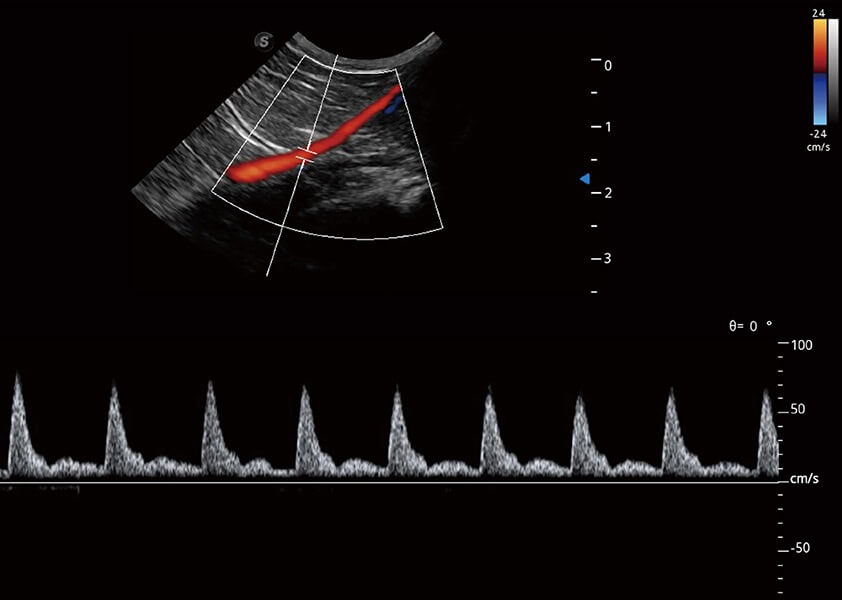

ProPet 60 作为一款高端台式动物超声设备,为动物医生的日常诊断提供了一系列贴合动物临床需求、解决临床实际问题的高级成像功能。凭借全系列高清探头,满足医生对腹部、心脏、生殖、浅表、肌骨等成像的所有需求,切实帮助您提升检查效率,提高诊断信心。

动物是人类最亲密的朋友和最值得信赖的伙伴。环球UG官网也一直致力于探索动物专用的超声影像解决方案。 全新推出的ProPet系列,是环球UG官网在动物超声影像智能化、专业化、精准化的一次跨越式革新。动物不能用言语来表述自己的不适,通过超声影像,ProPet系列搭建了动物医生与不同物种沟通的“桥梁”,为动物医生注入了“治愈之力”。